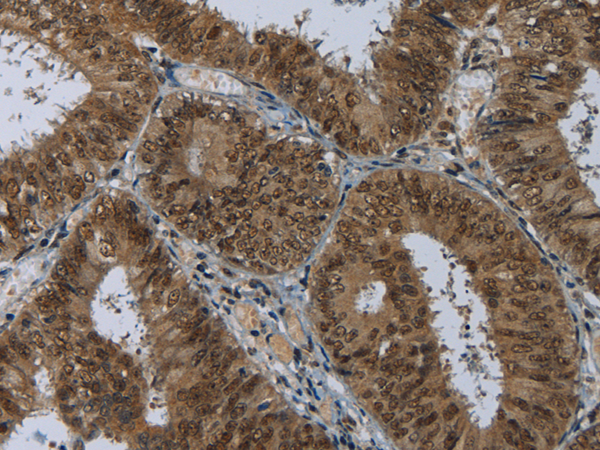

分类: 科研抗体货号: P01509别名: LCMT; PPMT1; CGI-68应用: IHC反应种属: Human, Rat